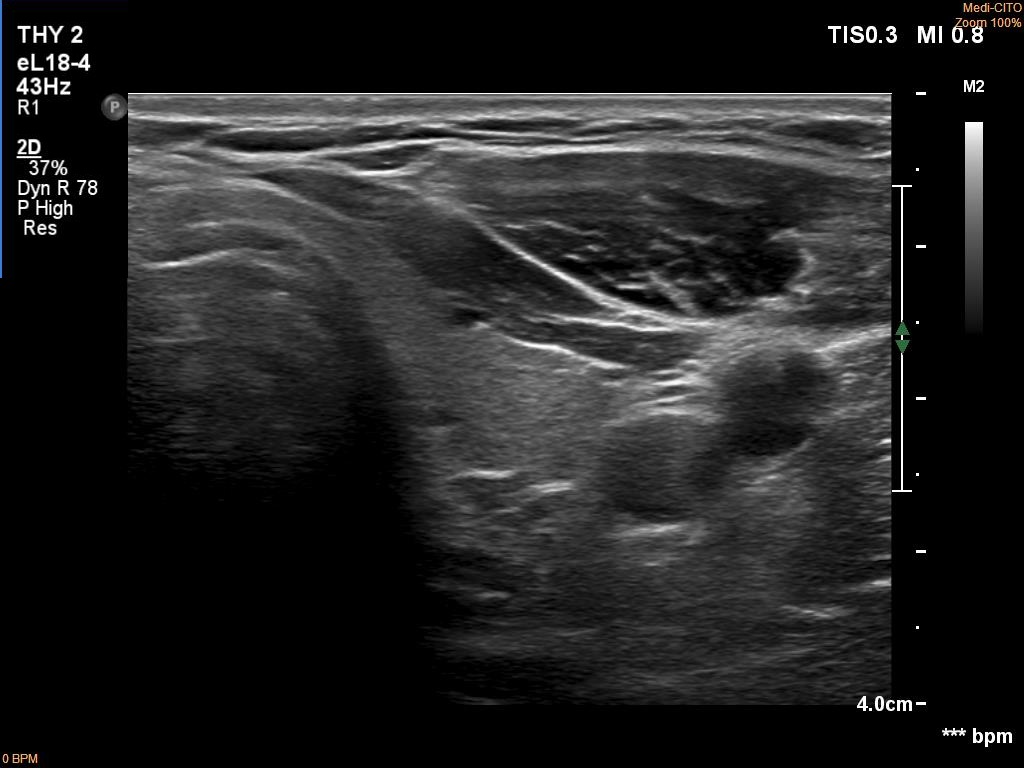

Ultrasonography. The thyroid was echonormal. There was a hypoechoic mass dorsal and under to the lower pole of the left thyroid lobe.

Comment. It is more difficult to gain adequate cytological material from a deep lesion than from a more ventral one.